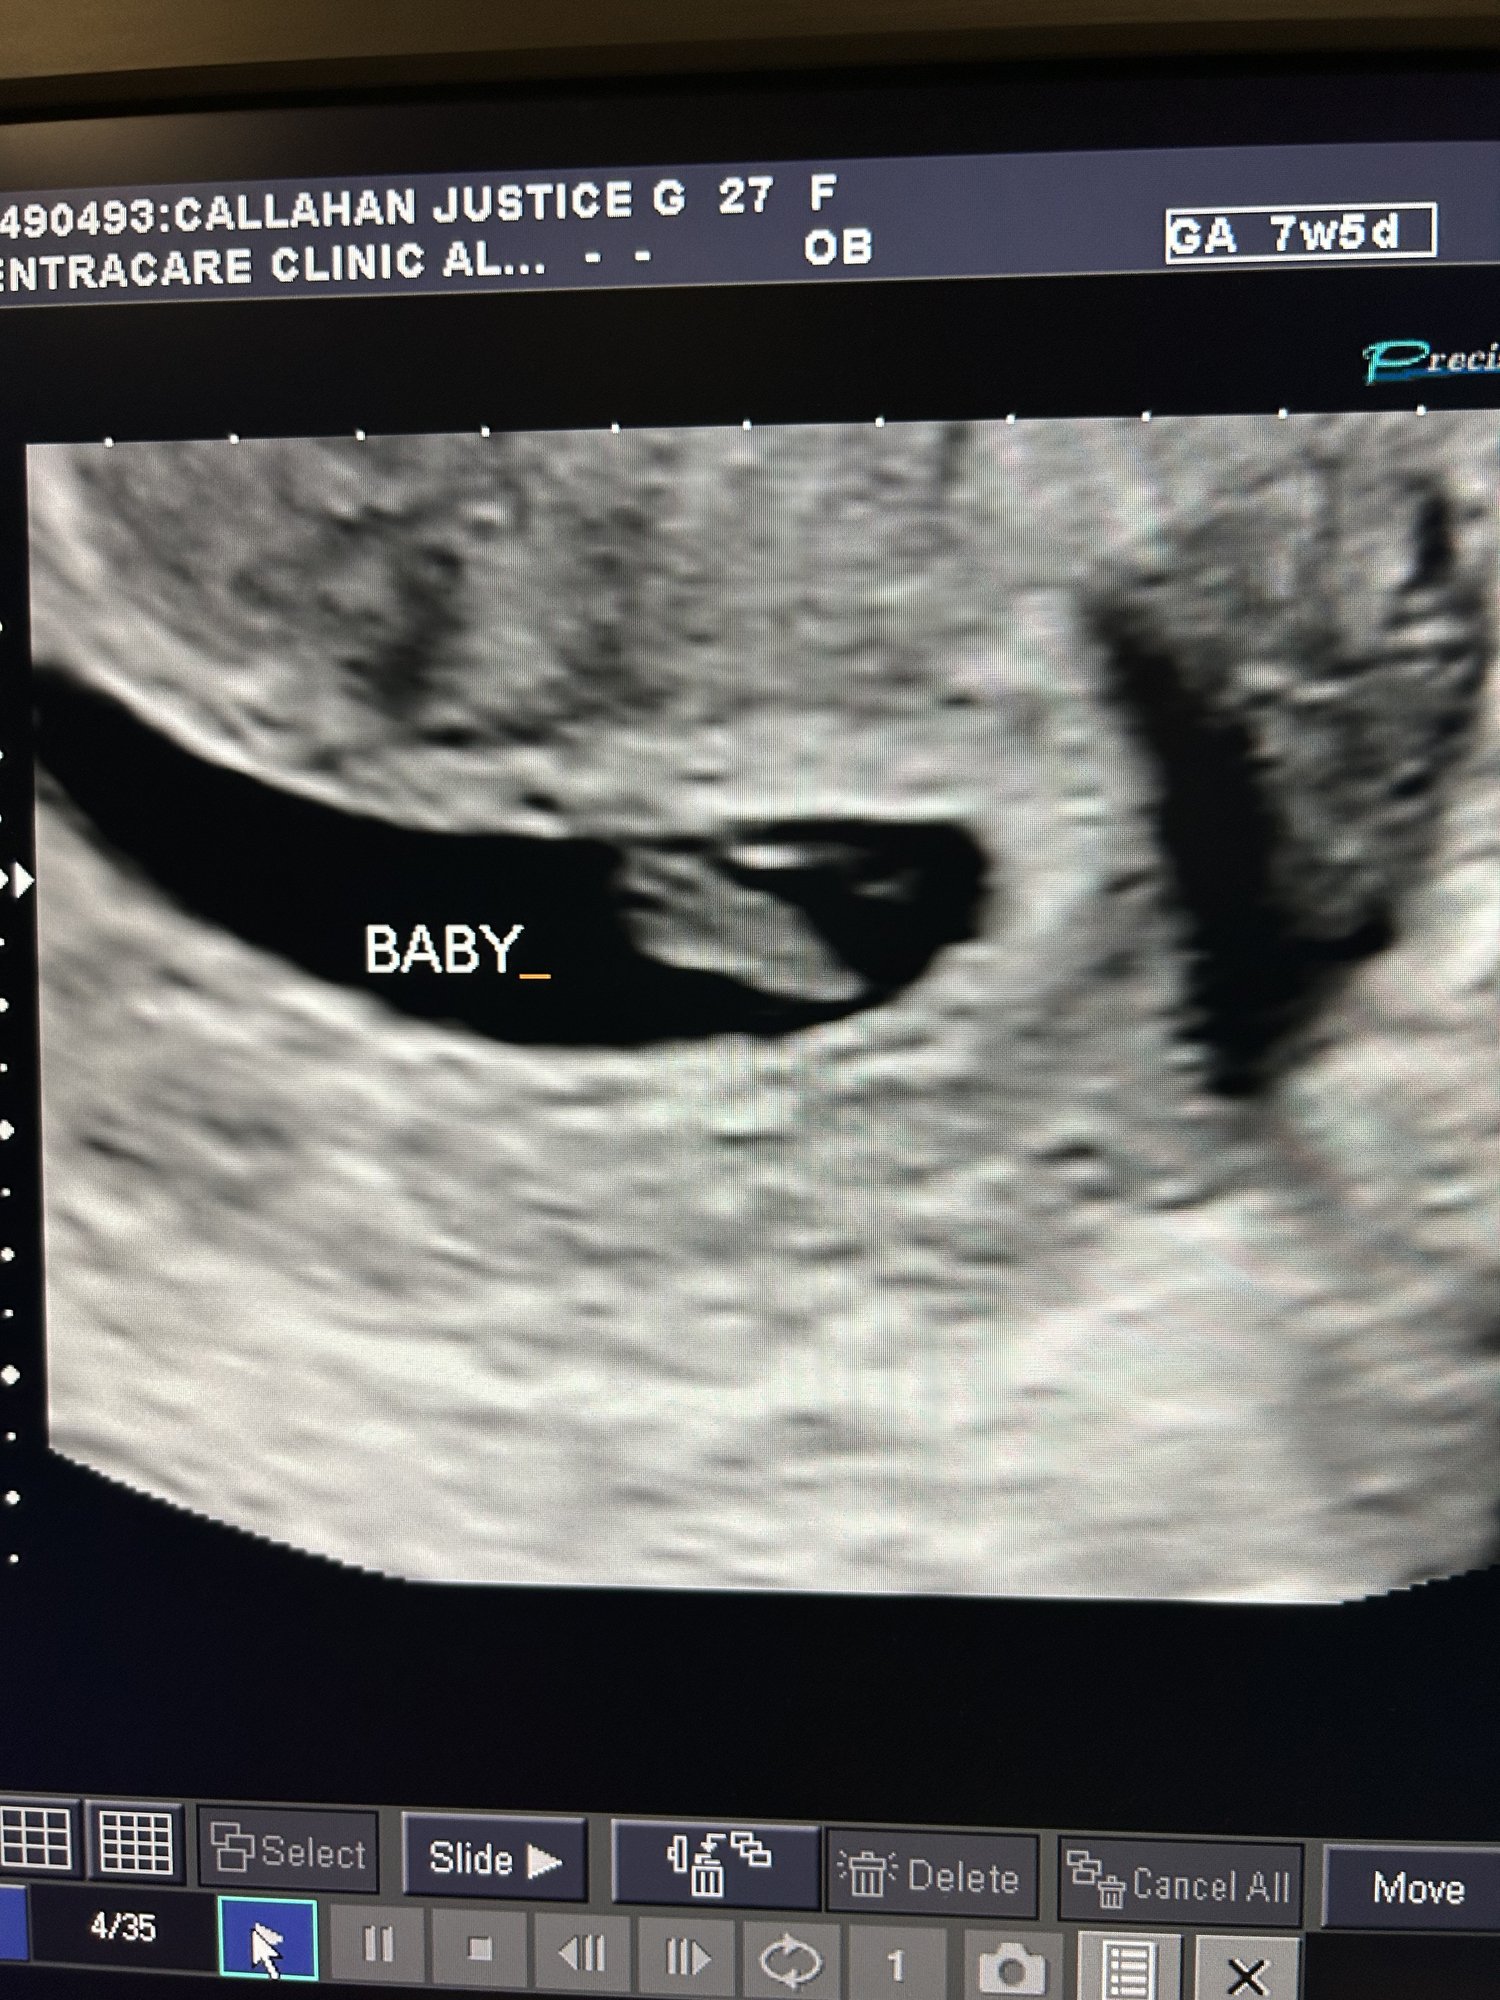

Got our ultrasound on the 21st at 7 weeks! 160 bpm and measuring exactly at 7 weeks! Next appt is in January and getting bloodwork done and to find out the gender 🤩